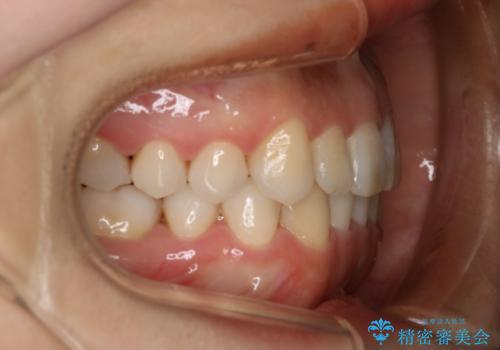

- 前歯のがたつきが気になるとのことで来院されました。

上顎の真ん中の歯の角度が、内側に傾いており、またその隣の歯が、唇側にずれてしまっていました。

下顎については、前歯にがたつきがありました。